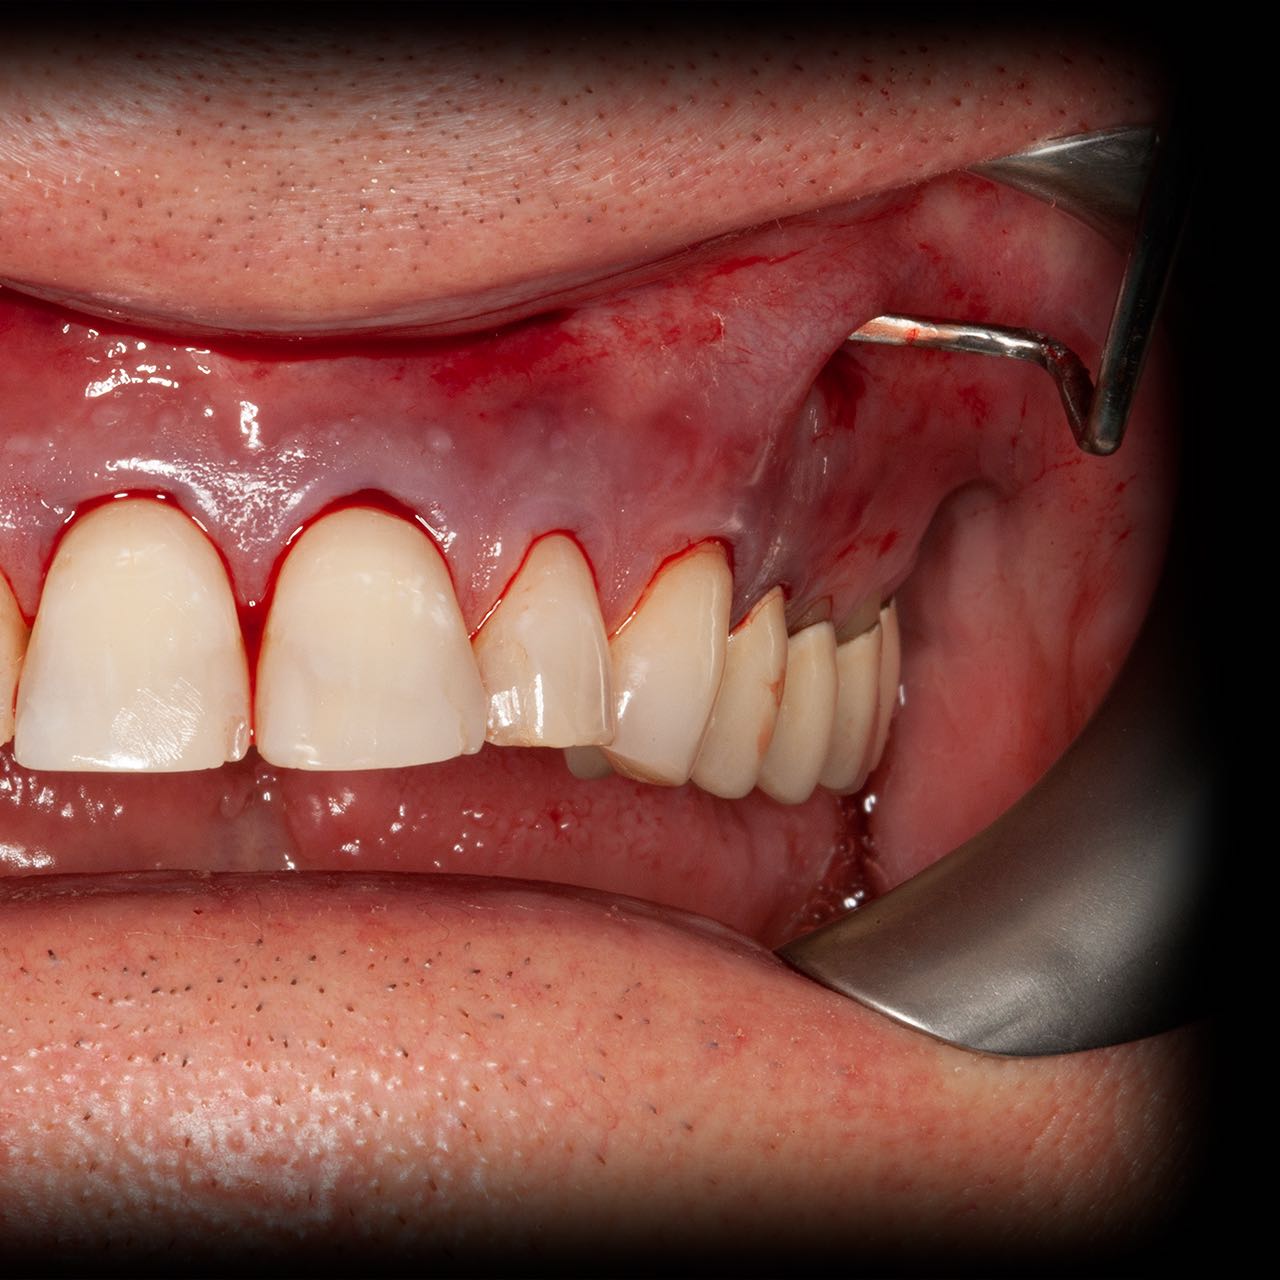

Operationsbilder Auch Operationsbilder anzeigen

• Zahnfleischaufbau, Deckung der freiliegenden Zahnhälse mit Bio-Material

Abdeckung der freiliegenden Zahnhälse (Rezessionsdeckung)